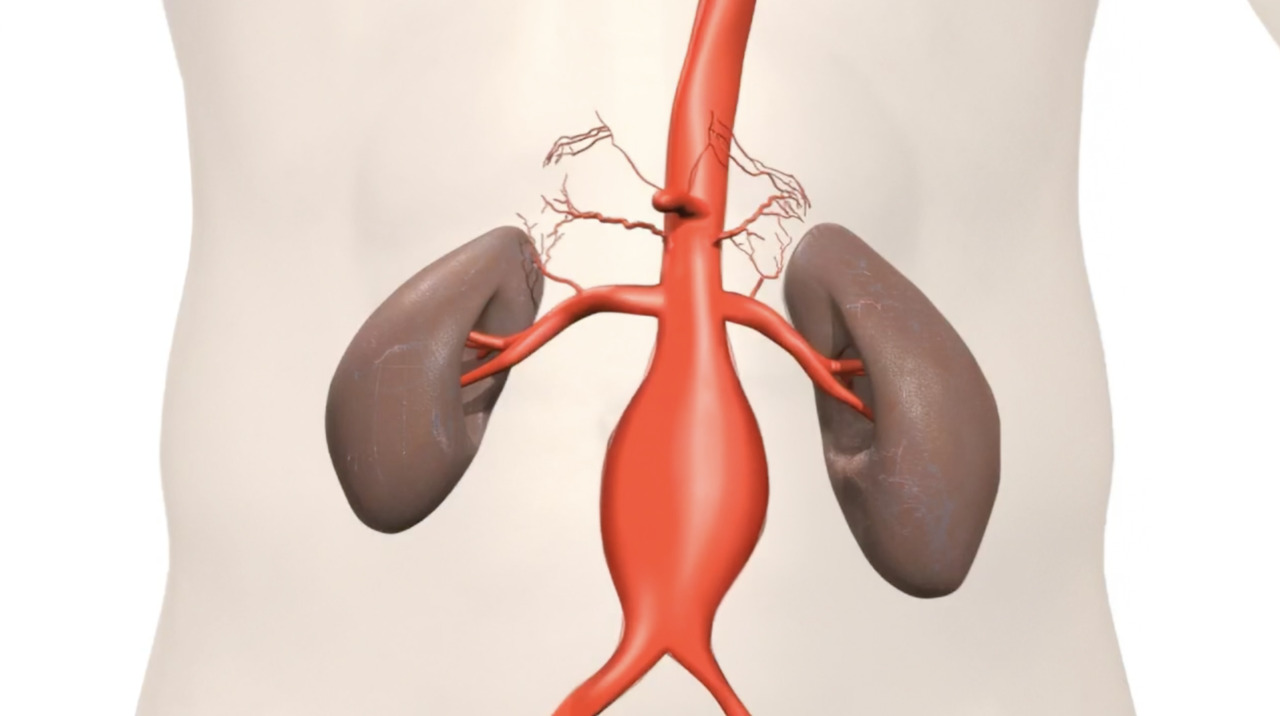

Endovascular Aneurysm Repair (EVAR/TEVAR)

A minimally invasive treatment that repairs weakened or bulging arteries.